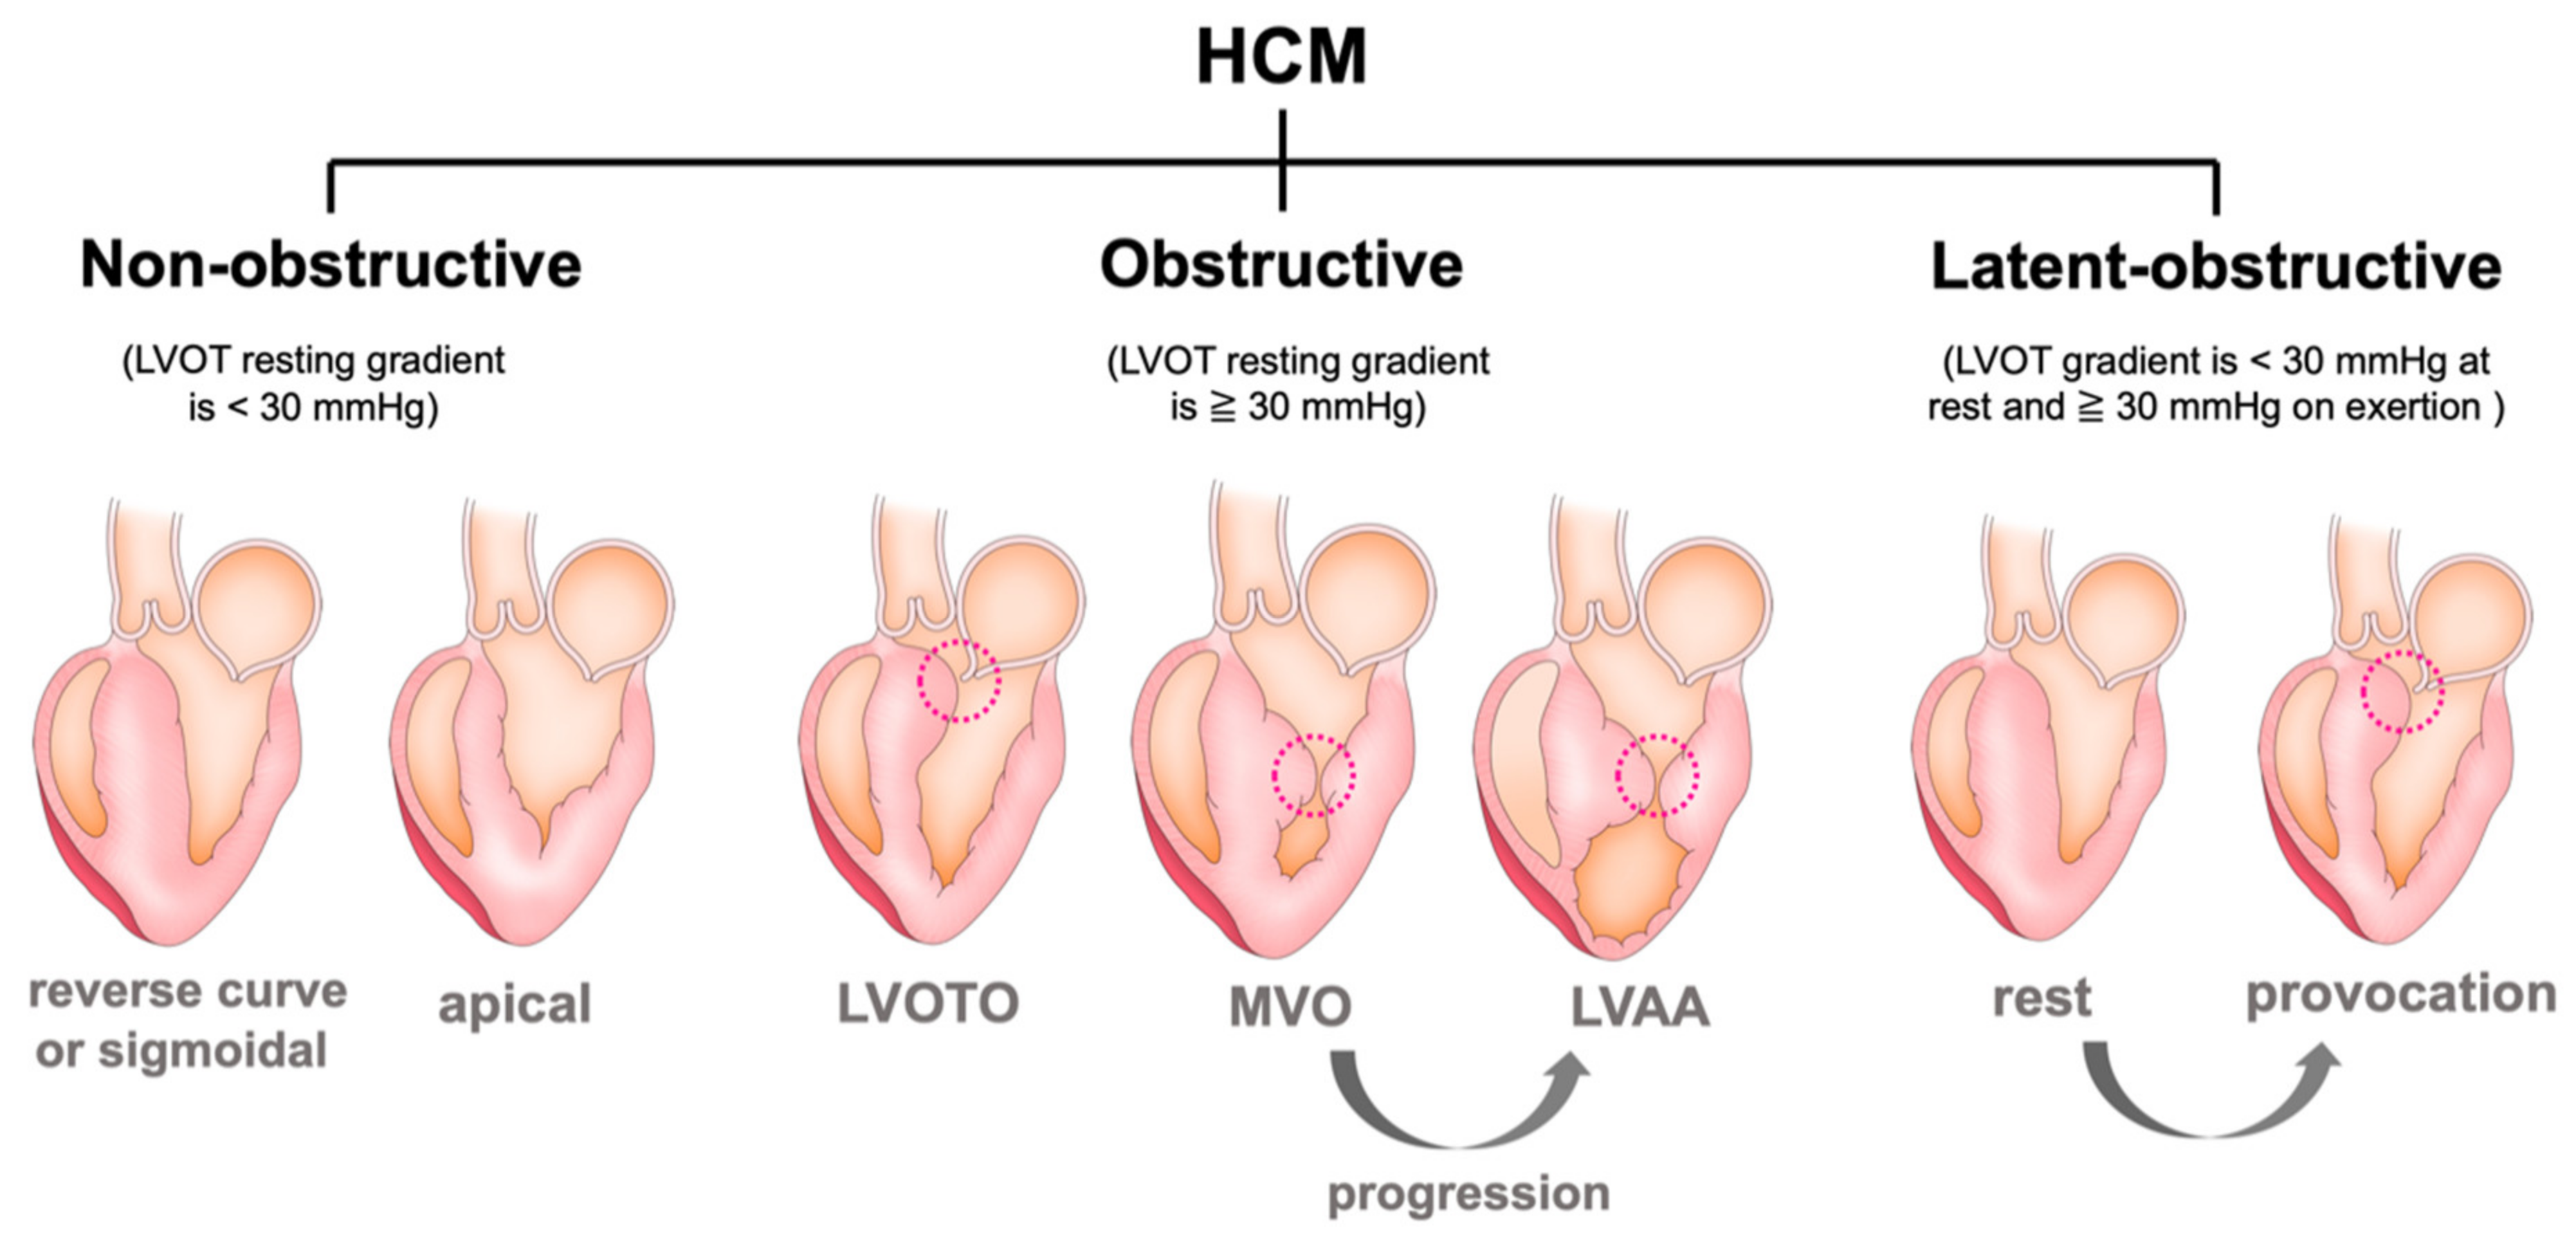

3. Various Types of Left Ventricular Structural Abnormality

3.1. Left Ventricular Outflow Obstruction (LVOTO)

3.2. Systolic Anterior Motion (SAM) of the Mitral Valve and Anomaly in the Mitral Valve Apparatus

3.3. Mid-Ventricular Obstruction (MVO) and Left Ventricular Apical Aneurysm (LVAA)